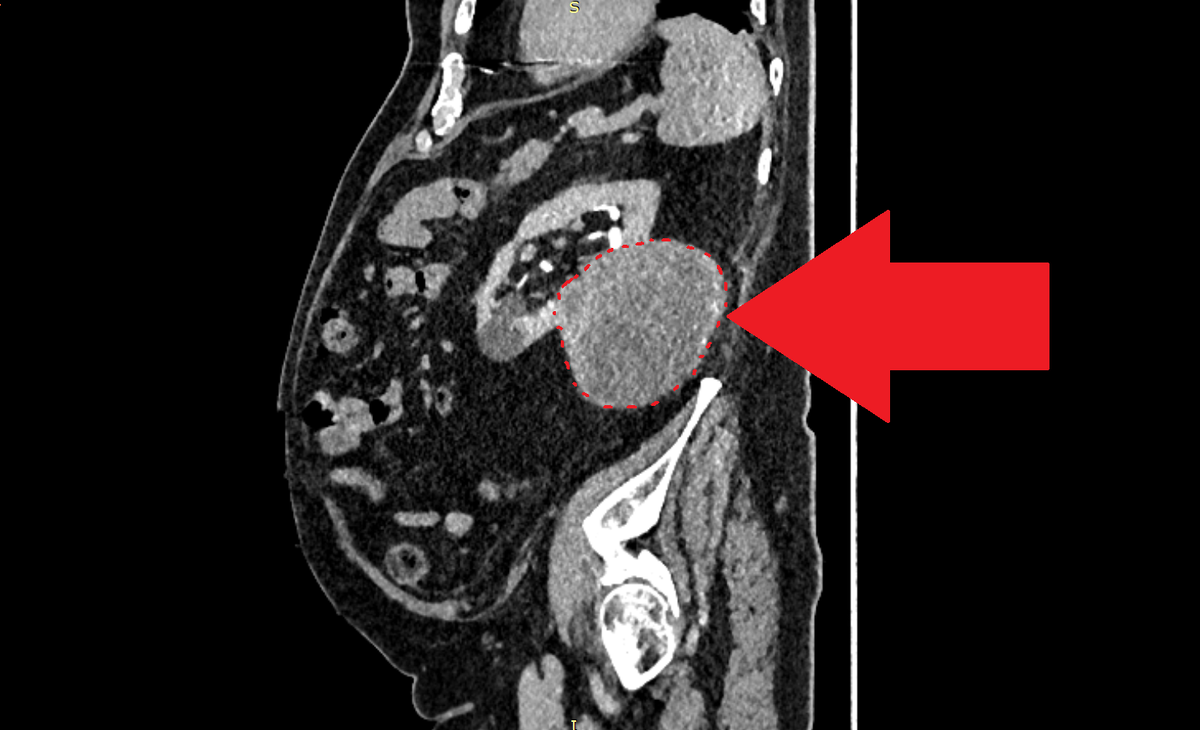

КТ с контрастированием. Стрелка указывает на опухоль, исходящую из заднего полюса левой почки. Новообразование таких размеров не вызывает боли у пациента.

Около трех лет назад во время УЗИ-исследования брюшной полости как случайная находка была выявлена опухоль, исходящая из заднего полюса левой почки. Размеры опухоли были более чем внушительные: 87х93х90мм, каких-либо жалоб при этом у пациента опухоль не вызывала. При комплексном обследовании признаков метастазирования выявлено не было. Учитывая свой возраст (79 лет на тот момент), пациент отказался от операции, а также от биопсии опухоли. Как пациент выразился в беседе со мной, «решил договориться с опухолью: я не трогаю её, а она не трогает меня»

Около трех лет назад во время УЗИ-исследования брюшной полости как случайная находка была выявлена опухоль, исходящая из заднего полюса левой почки. Размеры опухоли были более чем внушительные: 87х93х90мм, каких-либо жалоб при этом у пациента опухоль не вызывала.